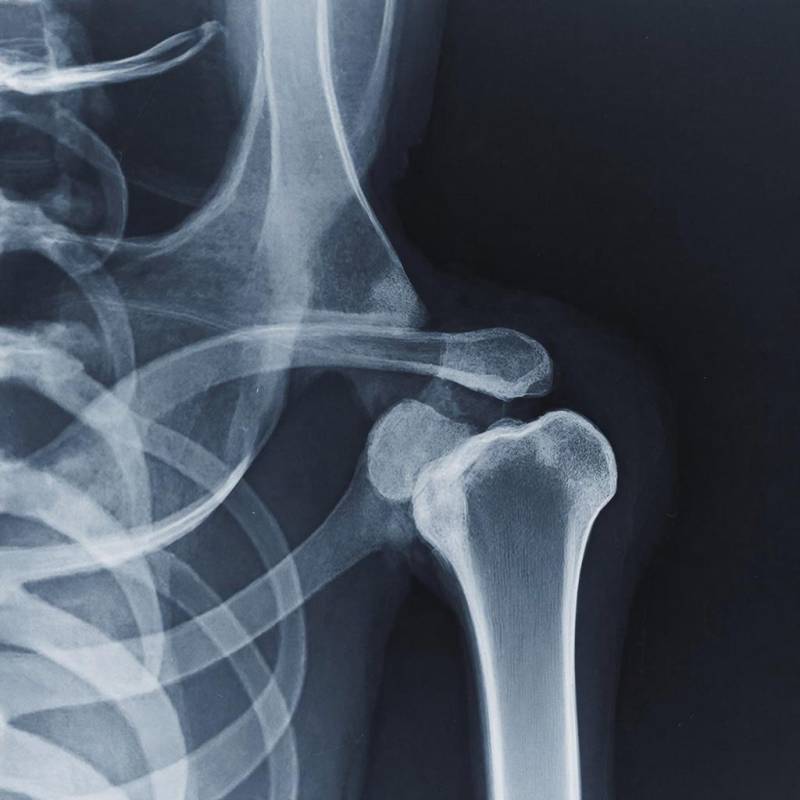

Новое исследование, проведённое специалистами из Университета Осаки (OMU), показало, что восстанавливать кости можно и при помощи жировой ткани. Это позволит изменить подход к лечению переломов и повысить прочность костей при остеопорозе.

В рамках нового исследования учёные использовали стволовые клетки, полученные из жировой ткани, развив их частично до костной ткани. Далее эти клетки собрали в сферические кластеры, которые и способствовали регенерации тканей.

У группы крыс, которую лечили остеогенными сфероидами, значительно увеличилась костная масса, улучшились показатели сращения и механическая прочность. Согласно гистологическому анализу, происходило усиленное образование новой костной ткани, интеграция β-трикальцийфосфата.